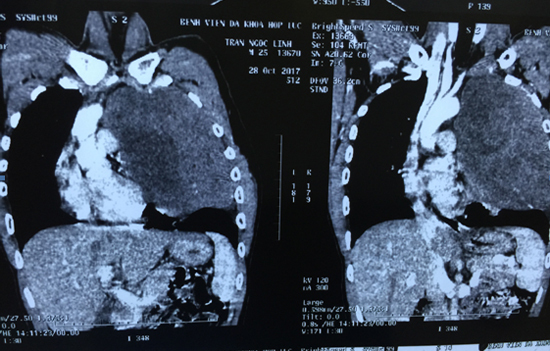

GS Thành cho biết, cách đây vài tháng, bệnh nhân có biểu hiện đau ngực, khó thở, thở gắng sức khi đi cầu thang và gần đây ho ra máu. Khi đến BV khám, bác sĩ phát hiện khối u tế bào mầm kích thước lớn trong lồng ngực, ở vị trí trung thất trước nên chèn ép tim, đường thở và mạch máu.

Theo GS Thành, khối u của bệnh nhân rất lớn, mật độ chắc, phát triển lan tỏa ra xung quanh vào khoang màng phổi 2 bên, chèn ép đẩy lệch khí quản, tim , phổi và mạch máu, u bọc quanh các dây thần kinh.

Đây cũng là vị trí cửa ngõ với các bộ phận sống còn của cơ thể: đường thở, đường ăn, mạch máu chính, tim phổi, dây thần kinh, trong khi khối u bọc quanh các thành phần này. Chỉ cần chạm phải một trong các bộ phận trên cũng dễ ảnh hưởng đến chức năng sống, thậm chí đe dọa tính mạng.

Bác sĩ chỉ định cưa mở toàn bộ xương ức, mở rộng lồng ngực để tiếp cận khối u. Sau nhiều giờ phẫu thuật, ca mổ hoàn tất, bóc tách được toàn bộ khối u nặng 700g và các tổ chức thâm nhiễm xung quanh. 6 tiếng sau mổ, bệnh nhân đã tỉnh táo, tự thở.